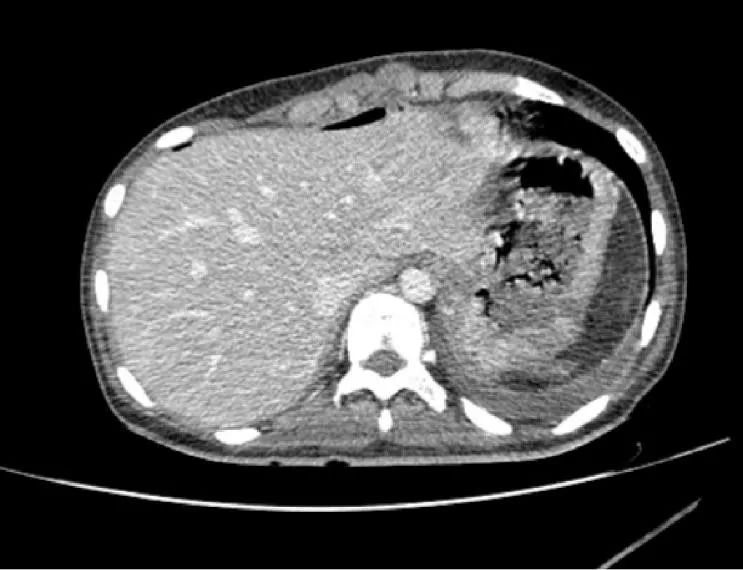

术前ct提示:脾破裂,肝周,脾脏周围积血手术过程中近年来,淄博市中心